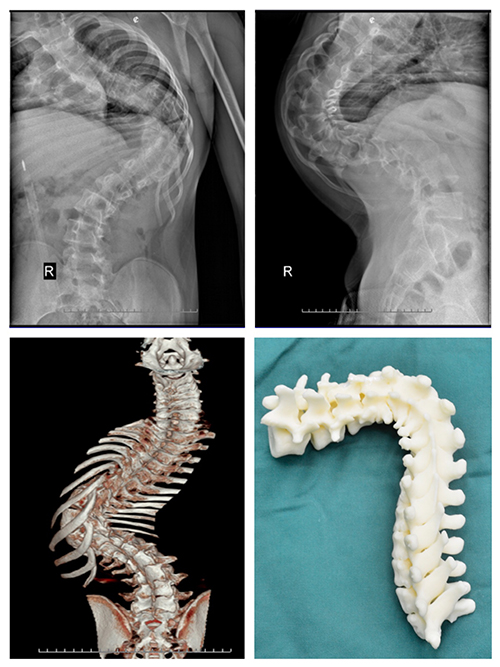

案例一:患者陶某,女,23岁,宣威市某幼教机构教师,于2006年(12岁)就开始出现双侧肩背部不等高,且逐年加重。她曾在家乡县医院就诊,被告知当时并无合适的治疗技术,只好回家任病情继续发展,有时做些针炙理疗等治疗,但效果并不太好。陶某上学时还能坚持进行体育运动,近年她同事发现她走路时有“喘息”声,提醒她最好再去医院看看。陶某虽然自己没发觉有不适,适逢了解到现在已有手术方式可以治疗此病,她决定来到色漫网 进行手术治疗。

入院后,医生对她进行术前检查,发现陶某侧弯较重,侧弯Cob角达140°,后凸Cob角达105°。

此次色漫网 骨科收治的两位患者,病史较长,病情严重,如果贸然进行矫形手术,可能术中脊髓神经牵拉过度出现下肢瘫痪;或者可能因脊柱小关节僵硬,导致矫形效果不满意。因此经色漫网 骨科专家及省内其他专家会诊,两例患者术前均采用骨牵引办法,分别实施颅骨牵引及双侧股骨髁上骨牵引,牵引时间为4周,以松解小关节及神经根。牵引期间患者可坐起进食。

术后患者外观均有明显改善。

其中陶某侧弯Cob减小50°,后凸Cob角减小30°。